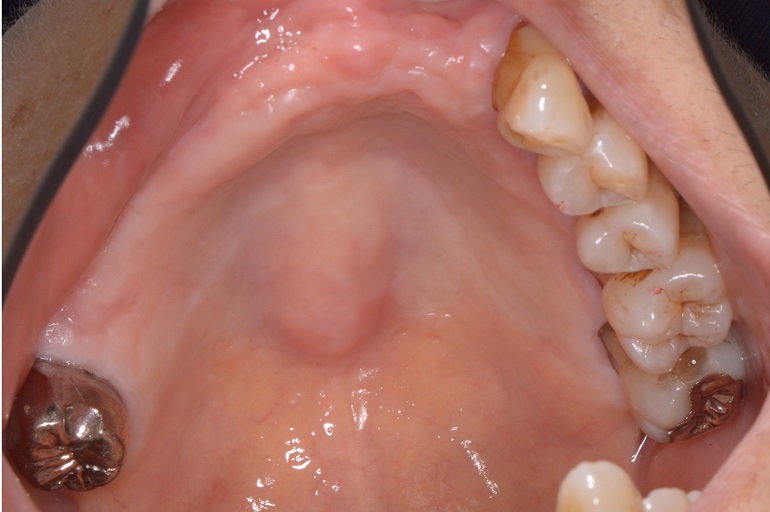

下顎

Before

After

| ①治療名 | ノンメタルクラスプデンチャー(スマートデンチャー) |

|---|---|

| ②治療説明 | 上下共に、欠損部を補うために、前歯にかかるバネが金属ではない素材を使用して義歯を作製しました。 |

| ③治療回数・期間 | 6回・2ヶ月半 |

| ④副作用とリスク | バネに金属は使用しませんが、見えにくい部分には金属を使うことがあります。また義歯を修理する際はお預かりして修理を行います。 |

| ⑤料金 | 60万円(5本以上のスマートデンチャー:25万円・メタルバッキング:5万円) |